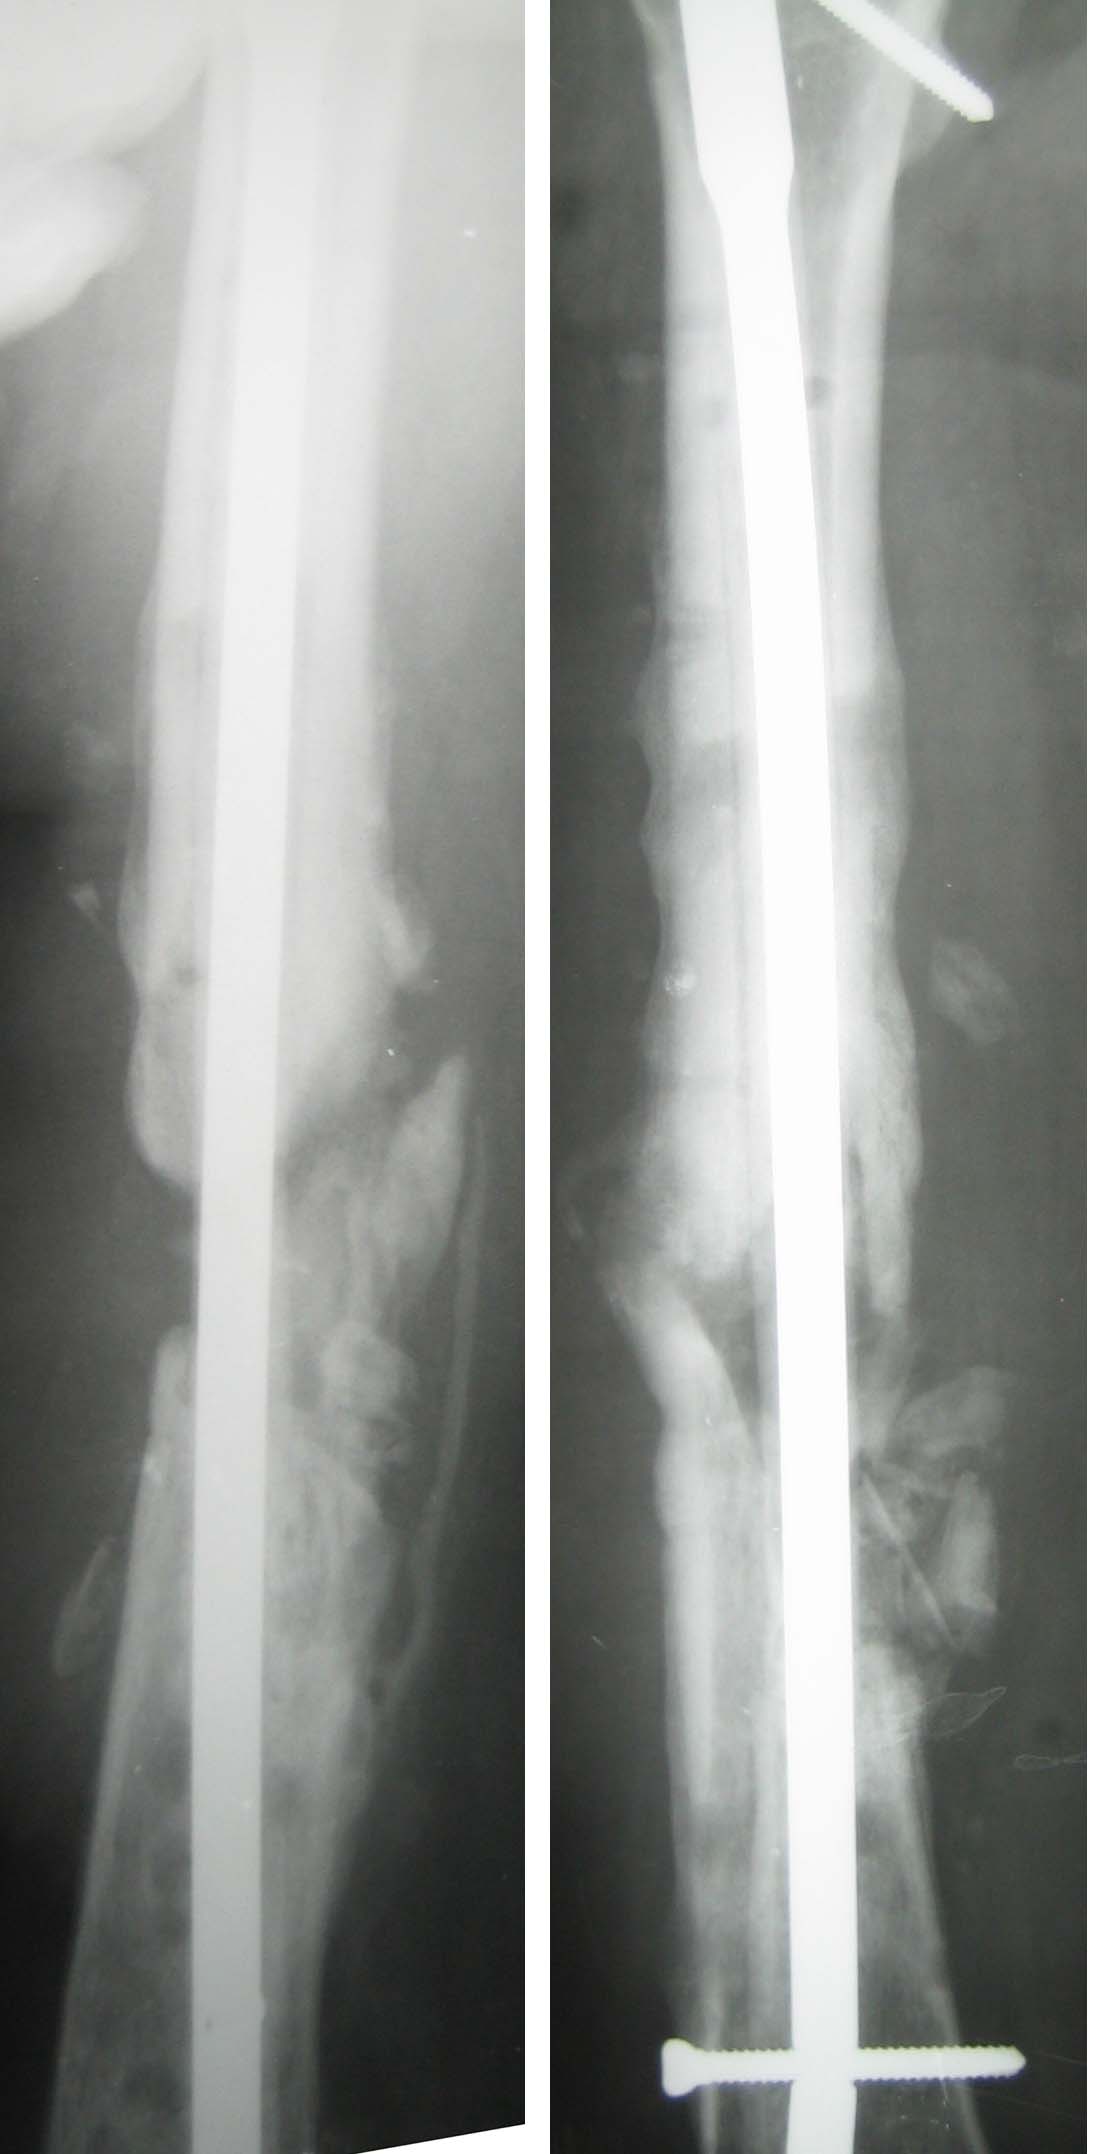

Продолжение случая.

Сначала разрезом около 10 см вскрыли зону ложного сустава. Мощные

рубцы, отсутствие инфекционных очагов. Особо углубляться не стали,

ушили рану, выполнили остеосинтез стержнем, предварительно покрыв его

цементом с антибиотиками.

Послеоперационные снимки - в приложении.